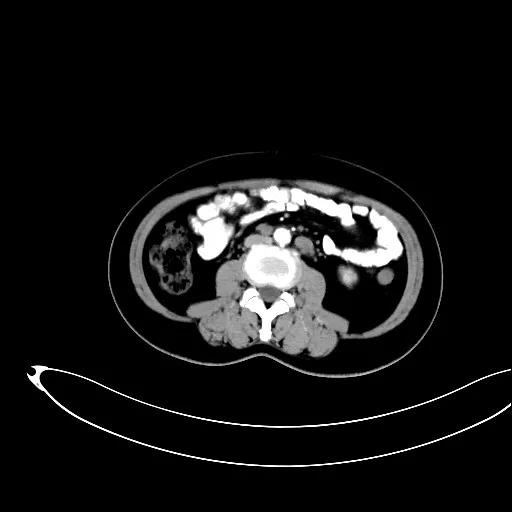

某患者因为“腹痛1周”而入院,外院B超提示子宫上方囊实性肿物,CT提示:左侧附件区占位,并盆腔及腹主动脉旁淋巴结转移。右肾动脉有右肾动脉及异位右肾动脉,其下均有肿大淋巴结。

排除禁忌后,在全麻下行“次广泛子宫切除+双附件切除+大网膜切除+阑尾切除术+盆腔淋巴结及腹主动脉旁淋巴结切除术”。术中切除腹主动脉左旁、右旁及后方淋巴结,达左右肾动静脉水平。多个淋巴结呈融合状态,长径约3-5cm。手术由陈亮副主任医师和宋趣清主治医师完成。

妇科一病区严格遵循指南推荐,在影像学或探查淋巴结阳性的晚期卵巢癌中,若能达到满意减瘤,仍常规行盆腔及腹主动脉旁肿大淋巴结切除/清扫术(如下图举例)。通过前期初步统计分析,肠系膜下动脉至肾静脉下淋巴结转移阳性率为25%左右,在全部腹主动脉旁淋巴结转移患者中约占30%,显示了肾静脉下腹主动脉旁淋巴结清扫的价值。其对生存的影响有待进一步观察。